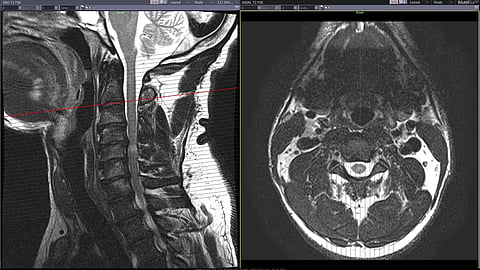

One kind of stimulation, called epidural spinal cord stimulation (eSCS), implants electrodes underneath the skin near the spine and sends electrical signals to stimulate specific muscle groups. In a spinal cord injury, neuronal communication from the brain to muscles in the body may be interrupted, but the connections from the spinal cord to the muscles themselves remain intact. ESCS can get extremely close to the spine and essentially allow the weakened signals from the brain to reach their targets in the spinal cord to reactivate the muscles.

Instead, Seáñez and his lab turned to transcutaneous SCS (tSCS). Instead of a surgical implant directly into the body, tSCS uses a series of electrodes placed on the skin to deliver electrical pulses with the aim of stimulating specific muscle groups. Researchers have studied tSCS for muscle stimulation for years, in a variety of configurations with both single electrode and multi-electrode arrays, but before this work there had been no comprehensive study evaluating how to best use tSCS for muscle stimulation.